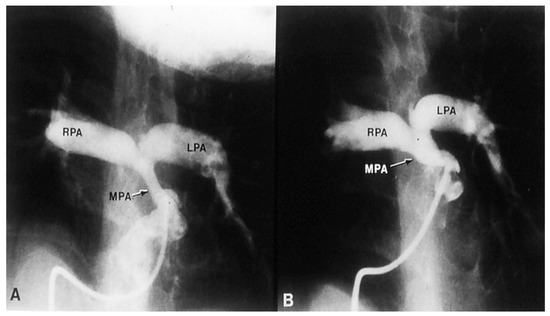

If the predominant obstruction is at the pulmonary valve level, though uncommon, balloon pulmonary valvuloplasty [12,13] to increase the pulmonary blood flow may be performed; balloon pulmonary valvuloplasty apart from increasing pulmonary blood flow, promotes growth and development of the pulmonary artery (Figure 2) and left ventricle so that a total surgical corrective procedure could be performed safely at a later time [12,13,14,15,16].

12. Rao, P.S.; Brais, M. Balloon pulmonary valvuloplasty for congenital cyanotic heart defects. Am. Heart J. 1988, 115, 1105–1110. [Google Scholar] [CrossRef]

13. Rao, P.S.; Wilson, A.D.; Thapar, M.K.; Brais, M. Balloon pulmonary valvuloplasty in the management of cyanotic congenital heart defects. Catheter. Cardiovasc. Diagn. 1992, 25, 16–24. [Google Scholar] [CrossRef]